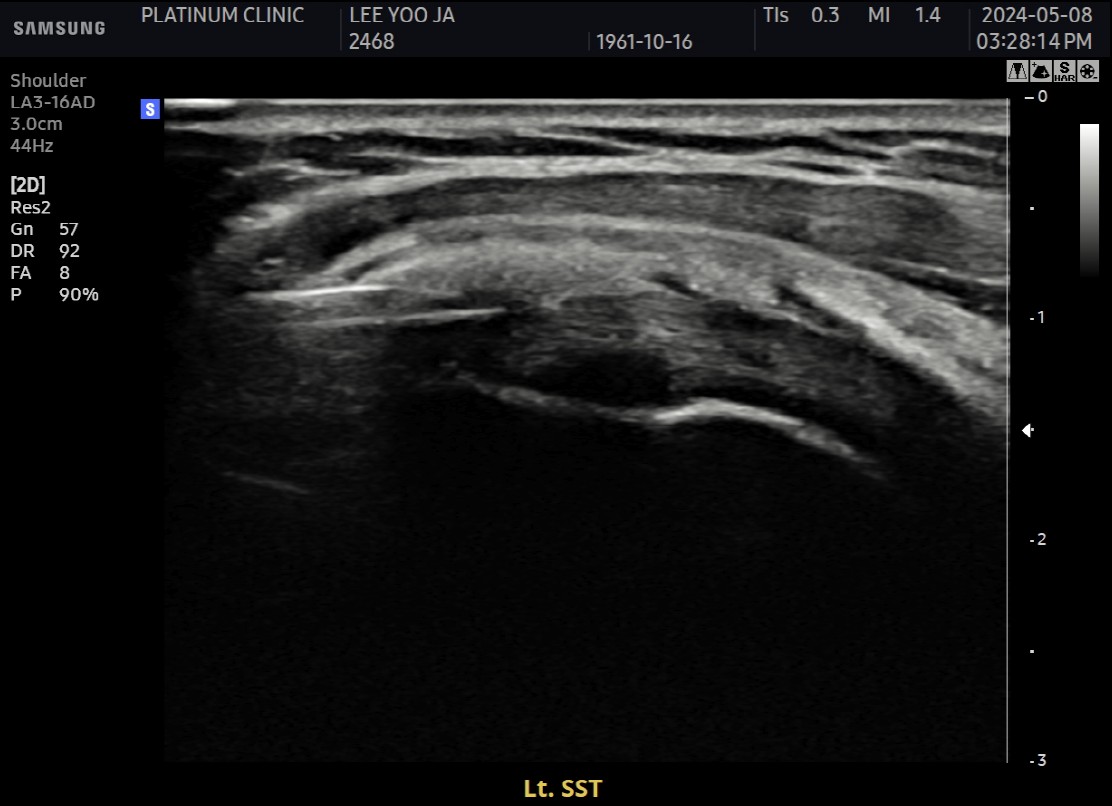

환자: 40대 여성, 좌측 어깨 야간통 1년

시술 전:

약 1.2cm 석회, 휴지기

충격파 10회 + 주사흡입술 2회 받았으나 호전 없음

시술 후:

1회 분쇄흡입술로 제거

야간통 소실, 수면 가능해짐

플래티넘에서의 치료

진단:

X-ray: 약 1.3cm 석회 (휴지기)

초음파: 석회 주변 인대 염증 소견

시술:

상완신경총 차단 마취

석회분쇄흡입술 시행

시술 시간: 35분

결과:

시술 직후 X-ray에서 석회 완전 제거 확인

기존 인대 염증은 재생주사로 추가 치료